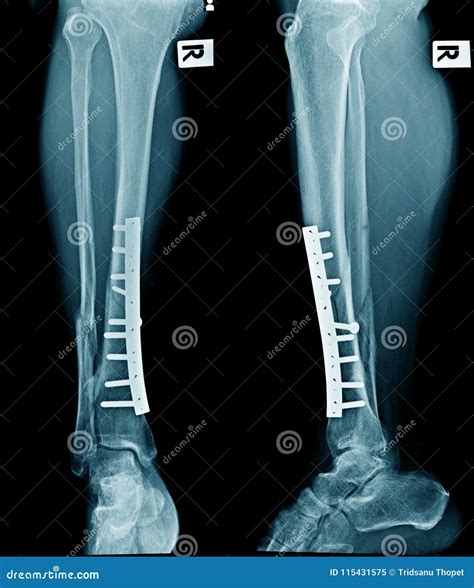

• Surgery: In cases of severe fractures or dislocations, surgical intervention may be required to realign the bones and stabilize the joint. This can involve the use of plates, screws, or rods.

Professional athletes often face significant challenges when dealing with tibia and fibula injuries. For example, a professional soccer player who suffered a tibial shaft fracture required surgical intervention and an extensive rehabilitation program to return to competitive play. The player underwent a series of physical therapy sessions, gradually increasing the intensity of training, and eventually returned to the field with no long-term complications.

Everyday injuries can also be severe and require proper management. A construction worker who fell from a height and sustained a distal tibia fracture underwent surgical fixation with a plate and screws. The worker then participated in a structured rehabilitation program, including range of motion exercises, strength training, and balance exercises, to regain full function and return to work.

Type of Injury Description Common Causes Treatment Options

Proximal Tibia Fracture Fracture near the knee joint, often involving the articular surface. High-impact trauma, falls, motor vehicle accidents. Surgical fixation, immobilization, physical therapy.

Shaft Fracture Fracture in the middle portion of the bone. Direct trauma, falls, sports injuries. Immobilization, surgical fixation, physical therapy.

Distal Tibia Fracture Fracture near the ankle joint, often involving the articular surface. Twisting injuries, falls, sports injuries. Surgical fixation, immobilization, physical therapy.